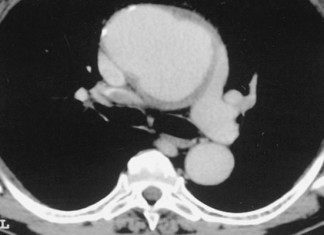

Reparación unica de un aneurisma aórtico muestra promesa

Un nuevo enfoque mínimamente invasivo parece ser seguro para el tratamiento de aneurismas potencialmente mortales que se producen en la parte más profunda de la...